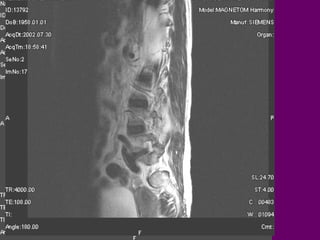

Di caên coät

soáng